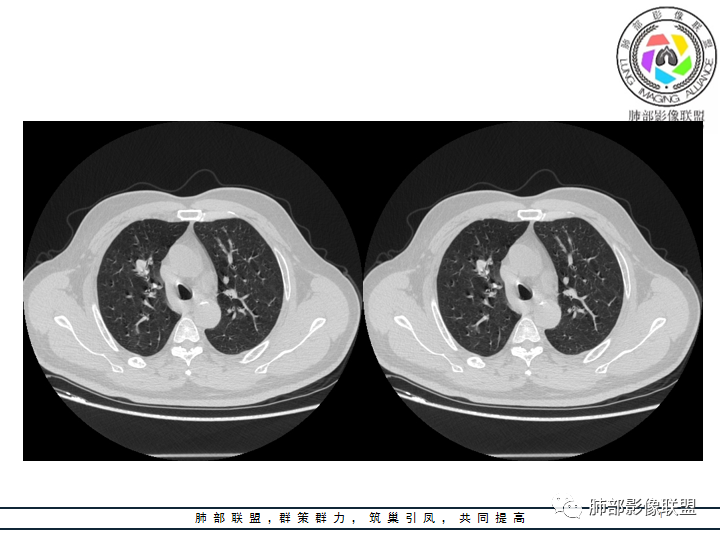

影像资料

老年男性患者,长期吸烟史,没有呼吸系统临床表现。胸部CT示右肺上叶实性密度结节影,密度均匀,未见空洞及钙化,边缘较光整,未见分叶及毛刺。血管影旁现侧出,支气管进入并截断,不均匀强化。

——本例鳞癌病理意见可以符合,只是太光整、太干净,且病灶不大,未能显示出坏死等特征,我们从影像上难以得出倾向性意见。